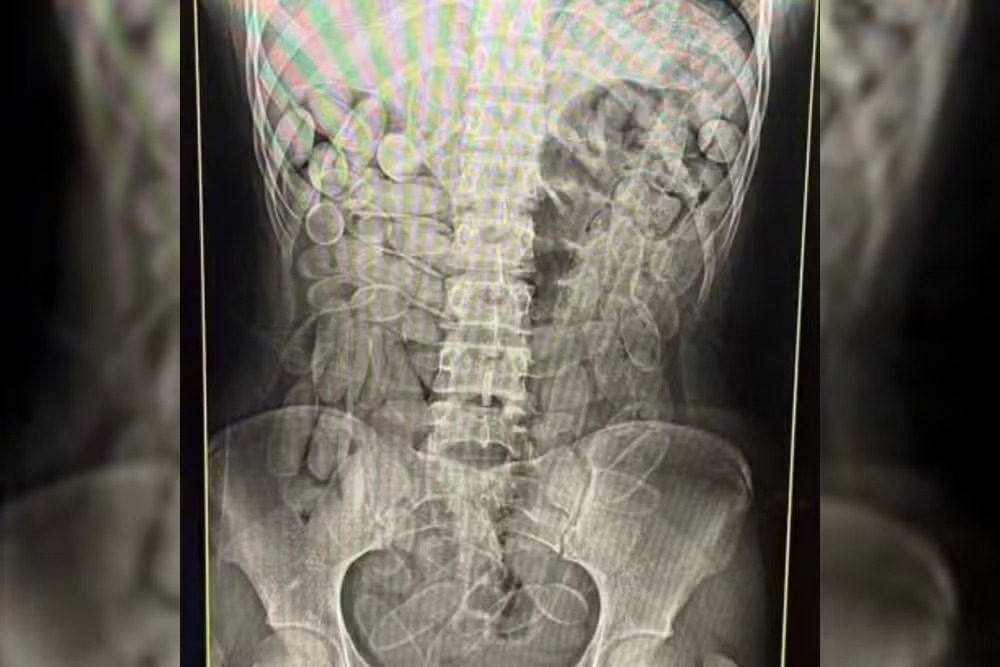

薬物の「運び屋」として摘発された女性のX線画像。体内運搬では、1人あたり平均約100個のコカインのカプセルを飲み込むとされる(Foto: Receita Federal)

ボリビアと国境を接するブラジル西部マット・グロッソ・ド・スル州コルンバ市。警察官の目前で、若い女性が突然コカインのカプセルを吐き出した――。体内に100個以上の薬物を隠匿して越境した彼女は、密輸組織に雇われた「人間運び屋(ムーラ)」だった。人体を「運搬容器」へと変える非道な手口が、国境地帯における麻薬密輸の深刻な実態を浮き彫りにしている。7日付のG1サイト(1)などが報じた。